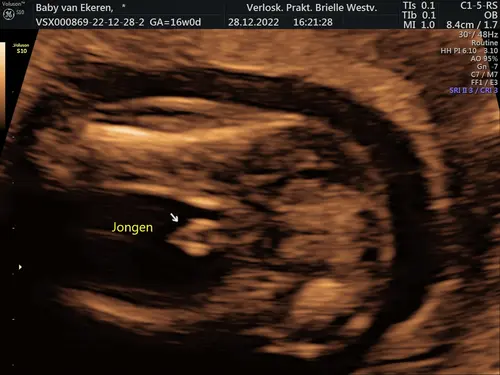

Vind je dit dan ook te groot?🤣 dit was met 13+6

Ik zeg niet dat ik te groot vind, ik heb er natuurlijk weinig verstand van en als de vk al twijfeld of het de navelstreng is of het geslacht dan is het logisch dat ik ook twijfels heb en ja in verhouding ziet het er "groot" uit..

Maar leuk dat je een jongentje krijgt en dat ze het duidelijk in beeld hebben kunnen brengen bij jou 😁

Dit is wel oprecht waarom onze verloskundige geen geslachtsecho’s maakt voor 16 weken😬 laat je weten wat het uiteindelijk is als je geweest bent?😘

Ik denk dat je geslacht en navelstreng op de foto naast elkaar ziet liggen. Navelstreng bij de cursor, geslacht er schuin boven

Wat een onduidelijke foto.. kan er weinig van maken😅 Wij hadden wel een beetje hetzelfde. Er lag duidelijk iets tussen de beentjes maar was heel lang en bewoog van links naar rechts. Leek af en toe een piemeltje als je t beeld stilzette. Bleek toch een meisje met de navelstreng tussen de beentjes te zijn☺️ Ben benieuwd wat t bij jou is!

Dit is die van ons met 14+2 - soms twijfel ik nog wel een beetje omdat “het” best klein is!?

Dit formaat was het bij ons 1e zoontje ook op de echo!😋